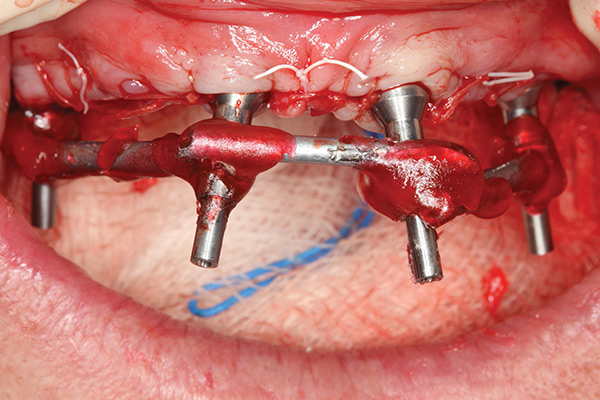

Fig 4. Placement of implants with straight multi-unit abutments on anterior implants and 30-degree angulated abutments posteriorly.

Figure 4

The transmucosal abutments are then placed onto the implants using either straight or 17-degree multi-unit abutments and 30-degree angulated abutments with different collar heights (Figure 4). Abutments should be orientated so that the screw access is in a favorable position. Bone grafts can be used to augment any exposed threads, extractions, sockets, or other localized defects. The tissues should be carefully repositioned and sutured to form a tight seal around the abutments.